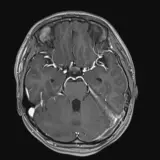

Over 2,100 interactive radiology cases, curated by radiologists for your level of training. Scroll, window, and view cases full screen — just like on PACS. Click linked findings in each writeup to jump straight to them on the image. Cases include sample reports, a focused discussion section, original illustrations, and videos.

Neuro Fellowship — a course tailored for fellows and practicing radiologists with in-depth reviews of advanced neuro topics like brain tumors, featuring rare diagnoses, differentials, and clinical pearls.